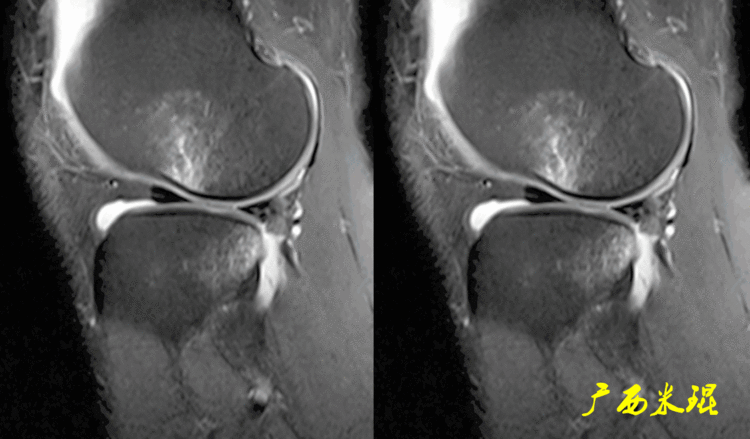

(2)隐窝隐窝是半月板后角与关节囊之间的正常凹陷,与体位等有关,可有可无,一般情况下积液越多隐窝越大,有上下之分,下面这张MR矢状位片见到的是上隐窝,紧贴半月板、光滑、不连通是其特点,也是鉴别要点。

下面这张MR矢状位片见到的是下隐窝,也紧贴半月板、光滑、不连通。

隐窝需要与半月板囊肿鉴别,下面这张MR矢状位片见到的是内侧半月板后角损伤并囊肿形成,与隐窝是有明显区别的。

隐窝还需要与半月板关节囊分离鉴别,下面这张MR矢状位片见到的内侧半月板后角与关节囊完全分离,周围水肿,胫骨内侧平台后方骨水肿;而隐窝是不会连通的。